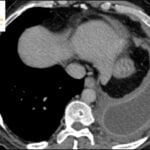

- Radiology Cases: Images with a to-the-point discussion highlighting the specific diagnostic criteria.

Latest Radiology Cases